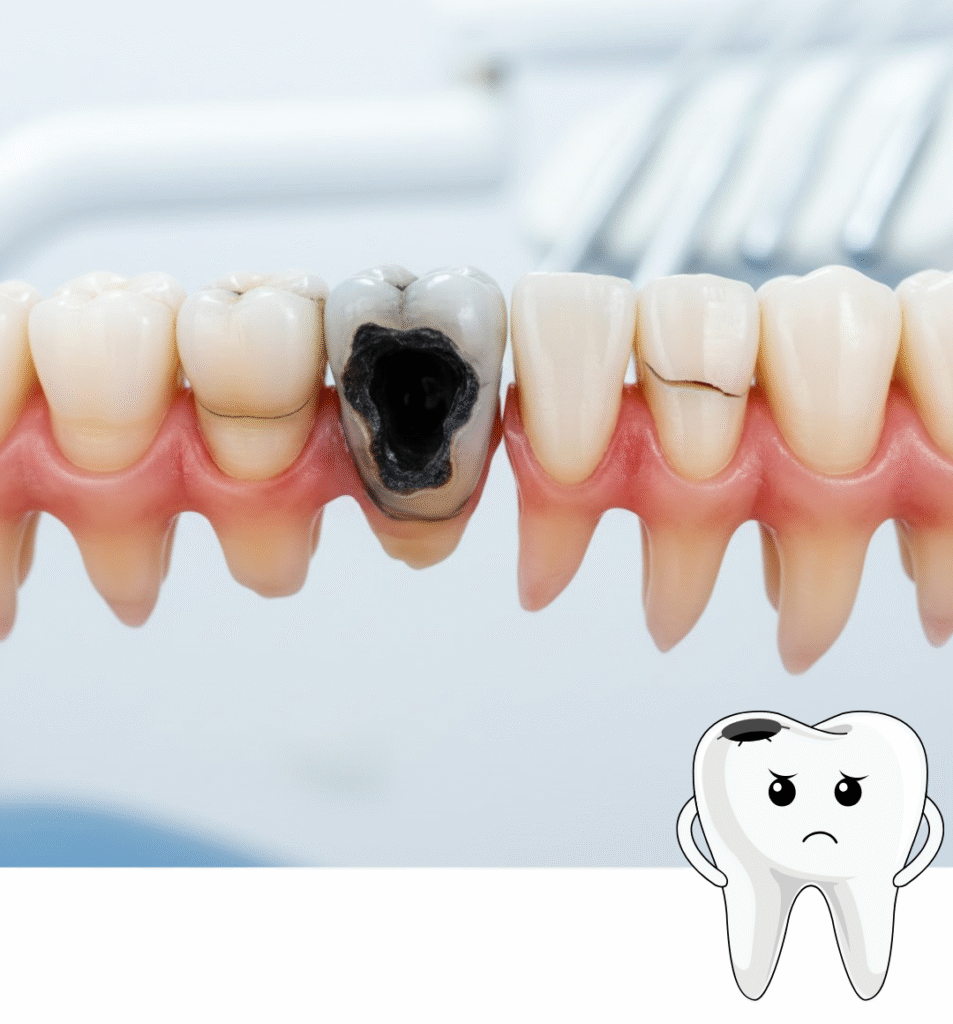

Message on WhatsApp Get AppointmentTeeth Extraction is a dental procedure to remove a damaged, decayed, or impacted tooth that cannot be restored through other treatments. At our Dental Clinic in Noida, extractions are performed using advanced, painless techniques by the Best Dentist in Noida to ensure maximum comfort and safety.

Whether it’s a wisdom tooth removal, infected tooth, or overcrowded teeth, our Best Dental Clinic in Noida offers precision-based extractions that protect surrounding gums and promote faster healing.

You may need a tooth extraction in the following cases:

If you experience pain, swelling, or pressure in your gums, visit our Dental Care Clinic in Noida for an expert evaluation.